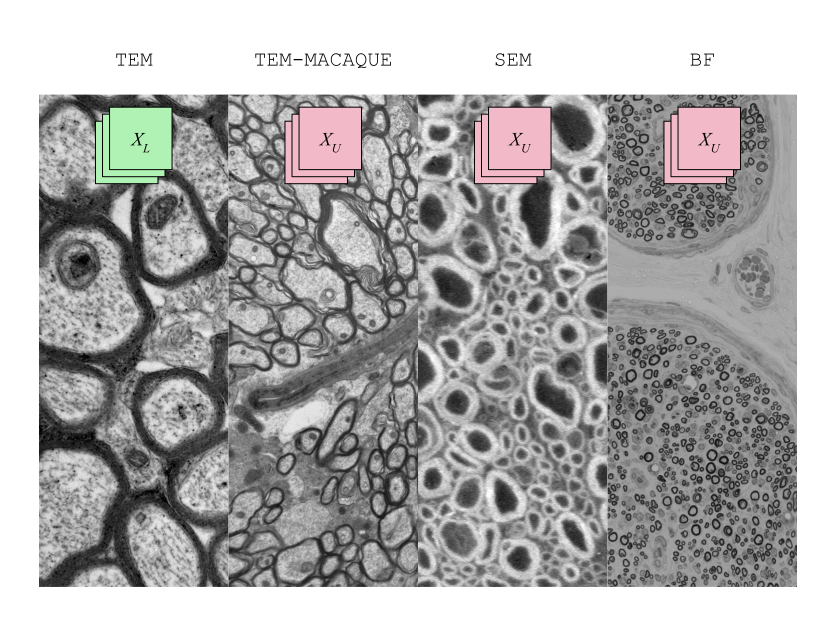

Figure S1: Datasets used, either annotated (XLsubscript𝑋𝐿X_{L}italic_X start_POSTSUBSCRIPT italic_L end_POSTSUBSCRIPT) or unannotated (XUsubscriptπ‘‹π‘ˆX_{U}italic_X start_POSTSUBSCRIPT italic_U end_POSTSUBSCRIPT). The TEM dataset is recycled for pseudo labeling in all three unlabeled domains.